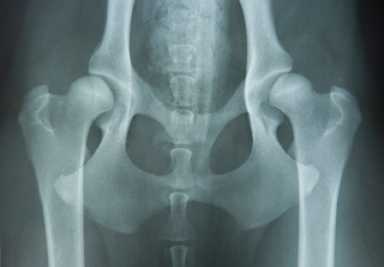

Dr. Weber is PennHip certified. This allows Dr. Weber to evaluate dogs, of any breed, for hip dysplasia using the PennHip technique. This technique measures hip distraction on a mathematical calculation rather than just subjective interpretation.

• Canine pre-breeding examination of females and males – this includes hip radiographs, general physical examination, temperament evaluation, brucellosis testing, semen evaluation, blood chemistry analysis, thyroid evaluation.

X-Ray of hips